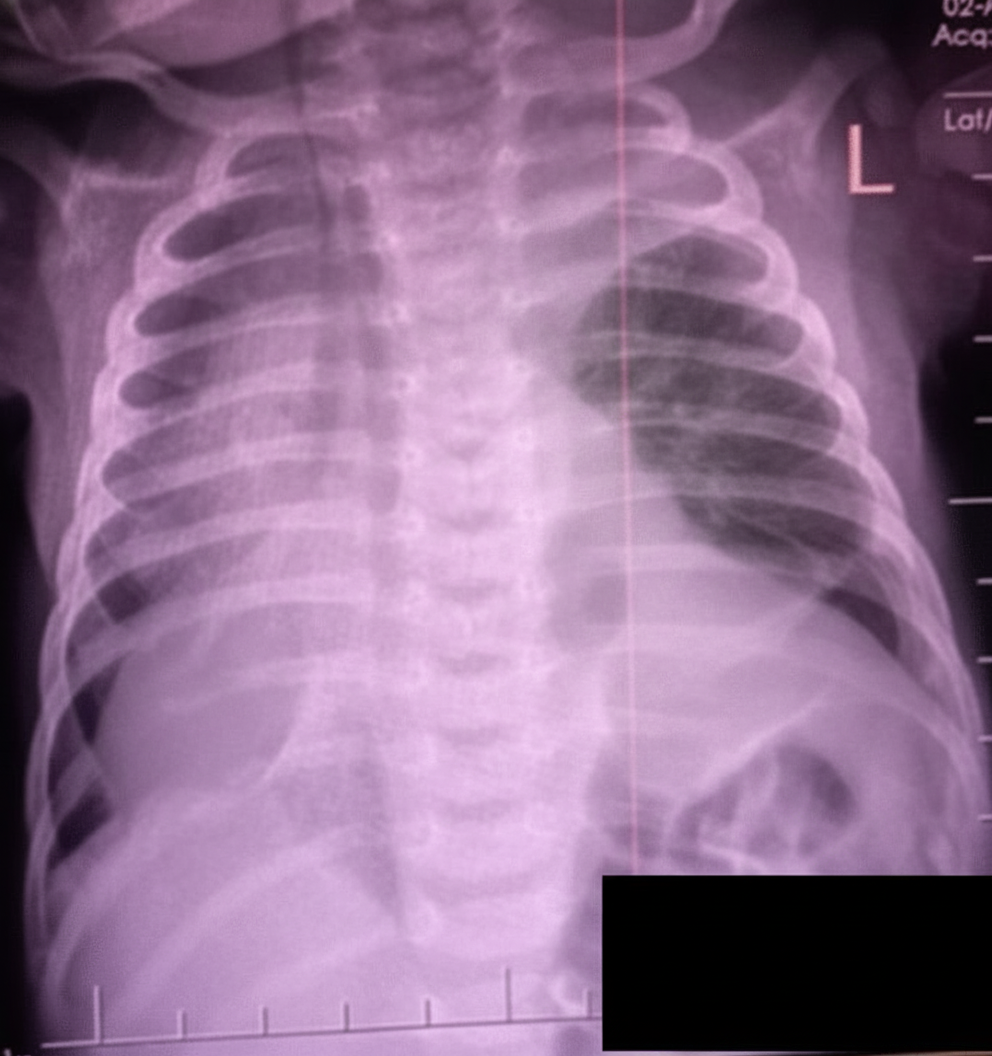

A 3-day-old child presents with the below CXR. What is the diagnosis?

Explanation: ***Congenital diaphragmatic hernia*** - Classic presentation in a **3-day-old neonate** with **bowel loops visible in the hemithorax** on CXR, causing **mediastinal shift** to the contralateral side. - Associated with **respiratory distress** and **scaphoid abdomen** due to abdominal contents herniating into the thoracic cavity through a **diaphragmatic defect**. *Pneumothorax left side* - Would show **hyperlucent lung field** with **absent lung markings** and **pleural line**, not bowel loops in the thorax. - Typically presents with **sudden onset respiratory distress** and **asymmetric chest expansion**. *Consolidation* - Appears as **dense opacification** with **air bronchograms** on CXR, not the characteristic bowel loop pattern. - Usually associated with **pneumonia** or **respiratory distress syndrome**, showing homogeneous density rather than tubular structures. *Congenital lobar emphysema* - Shows **hyperinflated lobe** with **hyperlucent appearance** and **compressed adjacent lung tissue**. - Presents with **progressive respiratory distress** but lacks the characteristic **bowel loops** and **mediastinal shift** pattern seen in diaphragmatic hernia.